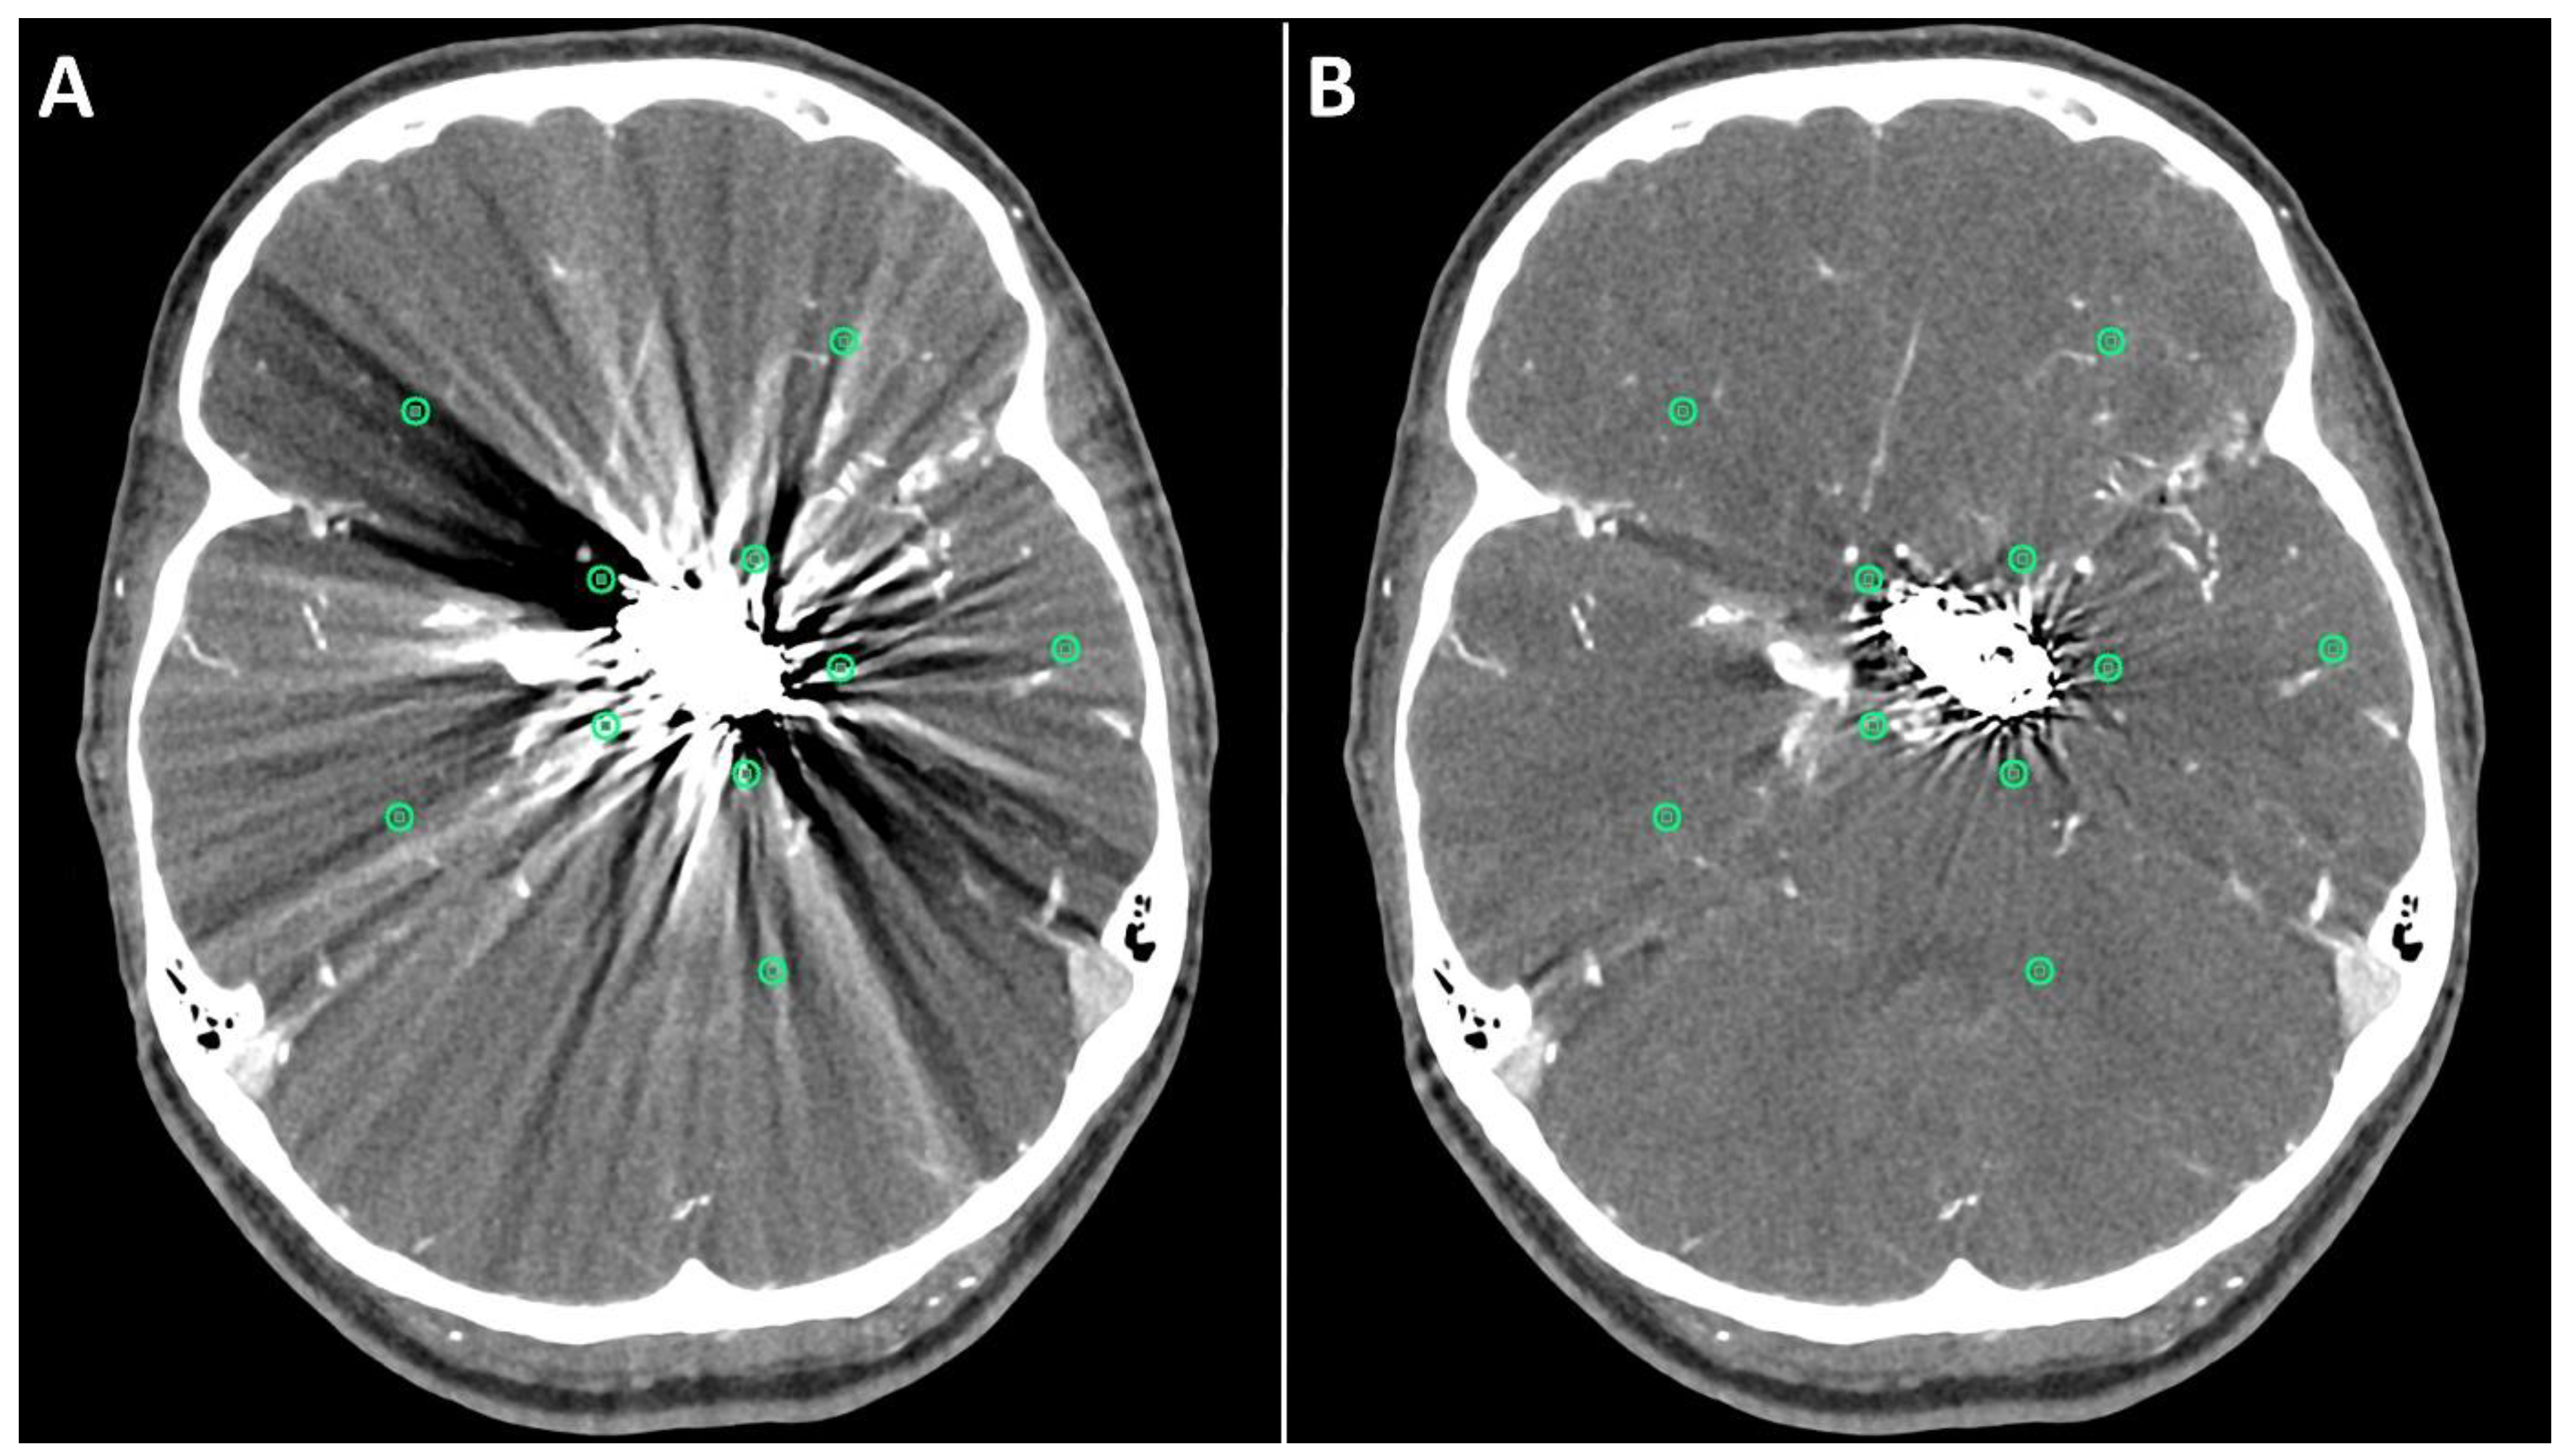

Figure 3.

Exemplary follow up UHR-CT-angiography in axial and coronal plane without (A,C) and with SEMAR (B,D) of a 48-year-old female after intracranial coil-embolization of a left sided middle cerebral artery aneurysm, demonstrate the efficacy of SEMAR in visualizing vessels adjacent to the coil package like the ipsilateral middle cerebral artery (thick arrow in (B)), the anterior cerebral artery (thin arrow in (B)), the ipsilateral posterior cerebral artery (arrowhead in (B)), and the middle cerebral artery (thick arrow in (D)). All images were reconstructed as MIP (Maximum Intensity Projection) with 12.5 mm slice thickness.